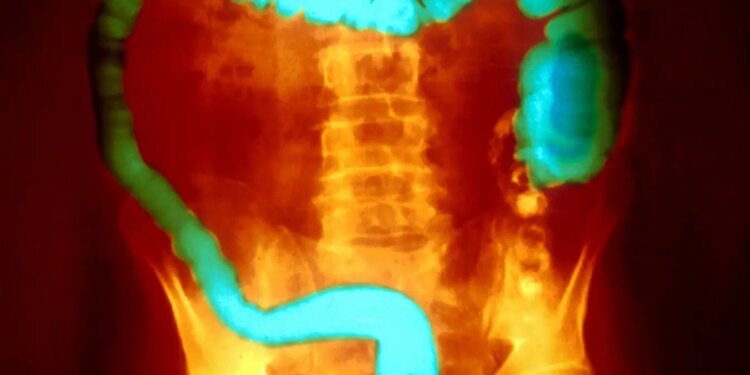

Ulcerative colitis is characterised by inflammation of the lining of the colon and rectum

Ulcerative colitis is one of the two main kinds of inflammatory bowel disease, or IBD. It is characterised by inflammation of the lining of the colon and rectum. People typically have periods of no symptoms that alternate with flare-ups. The most serious cases can require the removal of the colon.